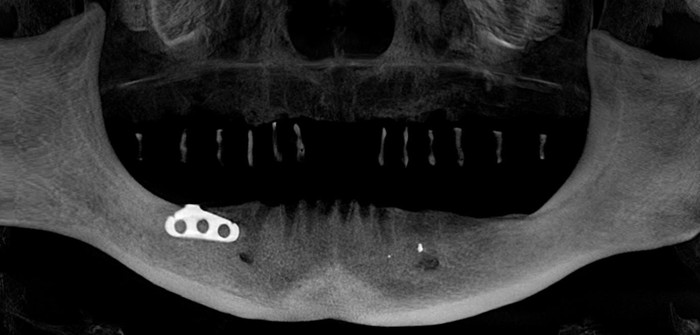

На верхней челюсти были установлены шесть имплантатов и проведена операция по наращиванию костной ткани – синус-лифтинг (с обеих сторон). Через 2 недели установлены 8 имплантатов на нижней челюсти.

Спустя четыре месяца были установлены формирователи десны на верхней (снимок слева) и нижней (снимок справа) челюстях.

Далее ортопедом были сняты слепки, а техник в лаборатории изготовил вот такой постоянный протез с опорой на имплантатах.

И, наконец, вот так выглядит протез в полости рта

Панорамный снимок зубов